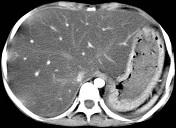

问题 男,57岁,肥胖、糖尿病、血脂升高,CT扫描如下图,请问诊断或描述错误的是哪一项 ( )

选项 A.肝硬化 B.脂肪肝 C.肝脏增大 D.密度均匀减低 E.血管影清唽可见

答案 A